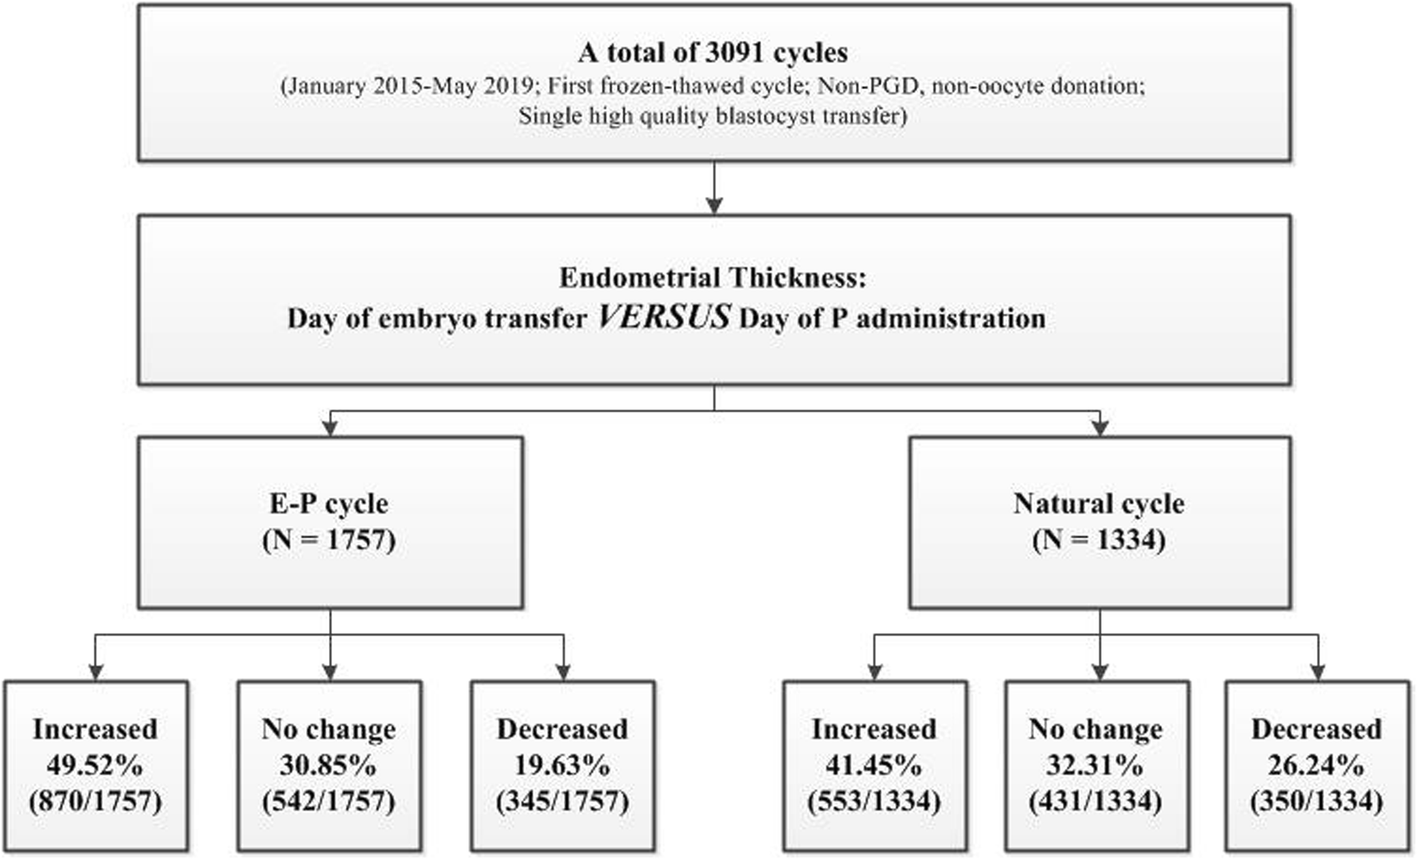

The Impact Of Endometrial Thickness Change After .